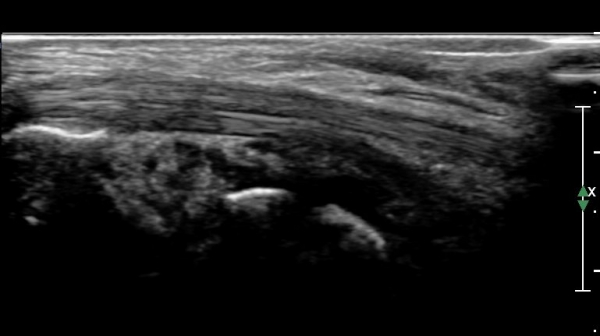

¹ß¸ñ ¿ÜÃø Ⱦ´Ü¸é(ºñ°ñ°Ç Ⱦ´Ü¸é)°Ë»ç¿¡¼­ ºñ°ñ°Ç ½ÉÃþÀÇ ´Ù·®ÀÇ ¼ö¾×Àú·ù°¡ °üÂûµÈ´Ù

(»çÁø 5, 6).